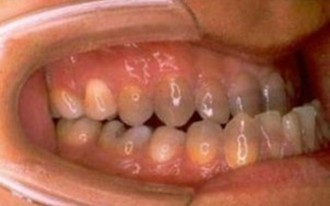

うまく噛めない、発音がしにくい、口が閉鎖できないなどの症状の他に、容貌が悩みの一つとなることも少なくありません。

口腔内側貌

手術前口腔内側面

手術後口腔内側面